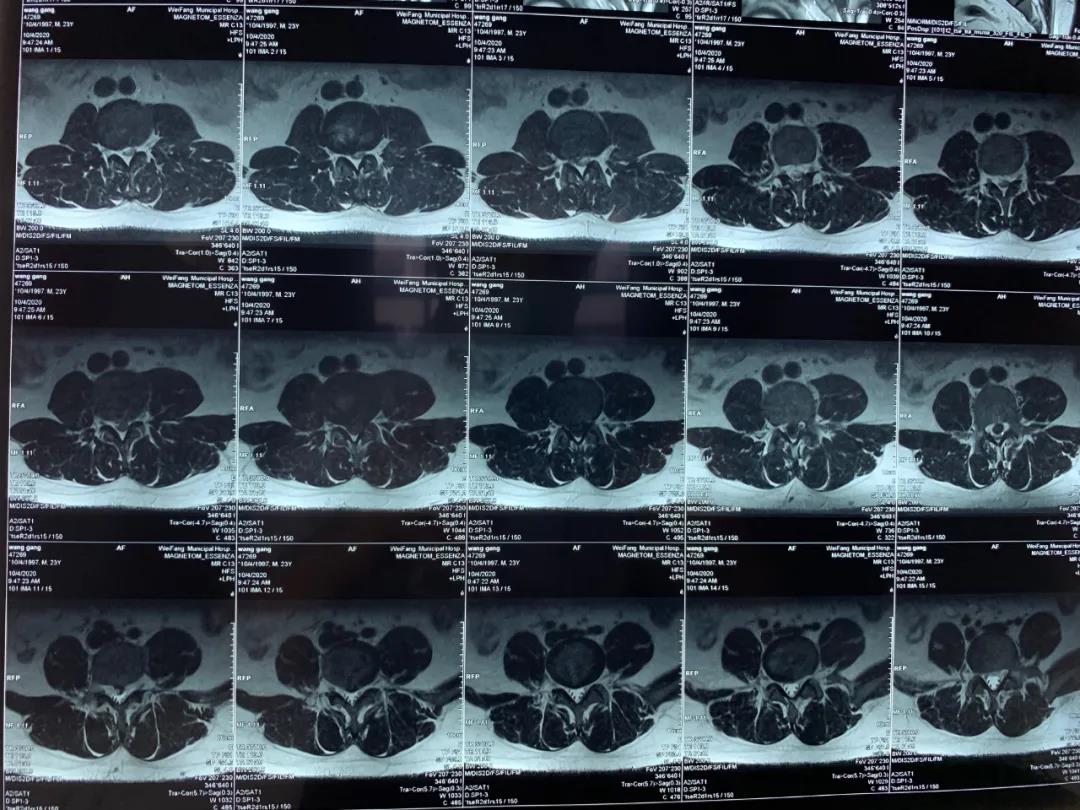

今年23歲的王先生因腰痛伴雙下肢放射痛及麻木不適2年加重5個月入院,入院后依據(jù)詳細查體和完善相關檢查,診斷為:腰椎間盤脫出癥,磁共振提示腰椎間盤巨大脫出。